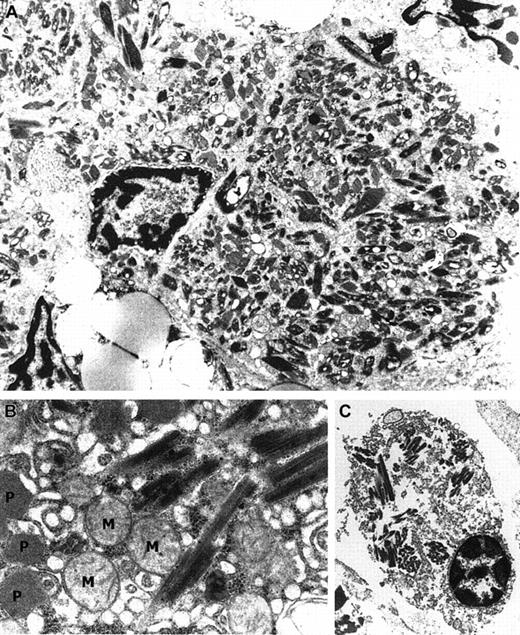

Electron microscopy showed crystalline inclusions in the macrophages of the bone marrow, liver, and skin. The electron-dense crystalline inclusions varied in dimension and structure. Rectangular and rhomboid shapes predominated. Similar inclusions were also detected occasionally in plasma cells of the bone marrow and in some hepatocytes (Figure 2A-B). No periodic organization of the substructure was observed.

Ultrastructure of different cell types containing crystalline inclusions.

(A) Kupffer cell containing rectangular and rhomboid crystals (× 10 000). (B) Similar crystalline intracytoplasmic inclusions in a hepatocyte. Note the mitochondria (M) and characteristic peroxisomes (P; × 21 000). (C) Geometrically shaped crystals in a plasma cell at the time of autopsy (× 5800).

In our case electron microscopy revealed crystal storage in the macrophages at different sites, just as described in the literature but without periodic organization of the crystalline substructure. Whether this is due to the composition of the stored proteins or the amino acid sequence of the immunoglobulins is unclear. Crystalline inclusions were also detected in hepatocytes as reported by Kjeldsberg et al23 in a case of MM associated with generalized CSH. Crystalline plasma cell inclusions were already occasionally seen in the initial bone marrow biopsy and at the time of autopsy when plasma cells were increased in number and fulfilled the diagnostic criteria of MM.